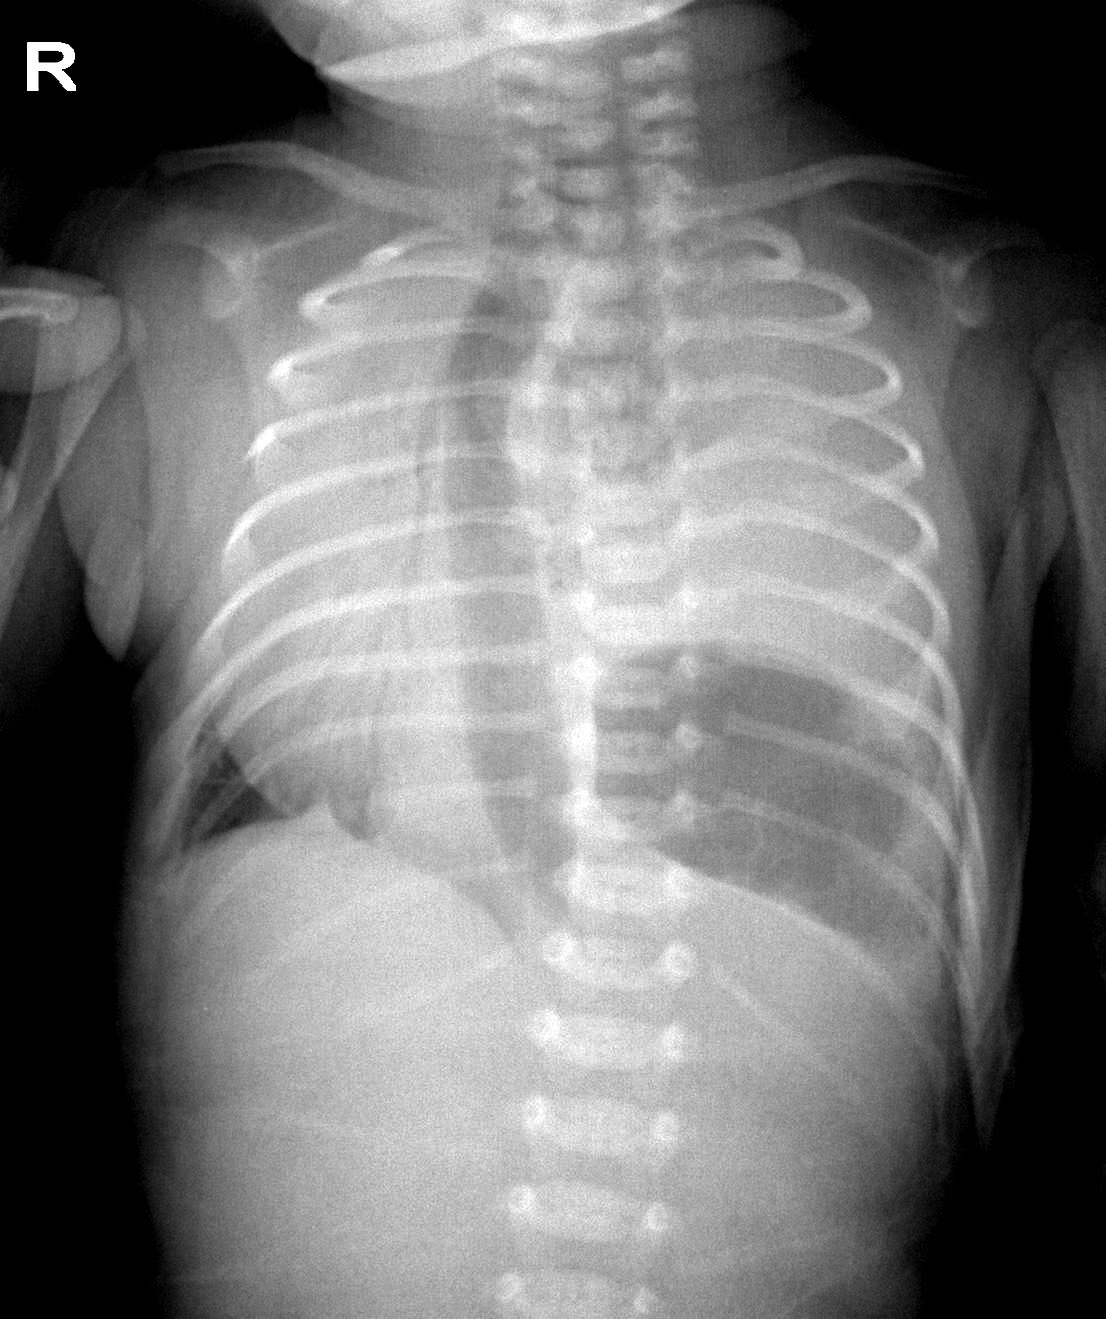

以下是引用余辉在2009-4-1 16:36:00的发言:[br]第一眼看起来是白肺,双侧支气管气像,考虑新生儿肺透明膜病,但是纵隔向右侧移位了,为什么移位,左侧压力较高或者右侧压力低,但是双侧肺都是白的,而且右侧膈角区有边缘清楚的肺膨胀区,这样又不太像透明膜病,患者胃泡膨胀且位置上升,考虑左侧先天性膈疝伴左肺不张,纵隔右移,右肺爱压,建议ct检查,不排消化道亦有畸形